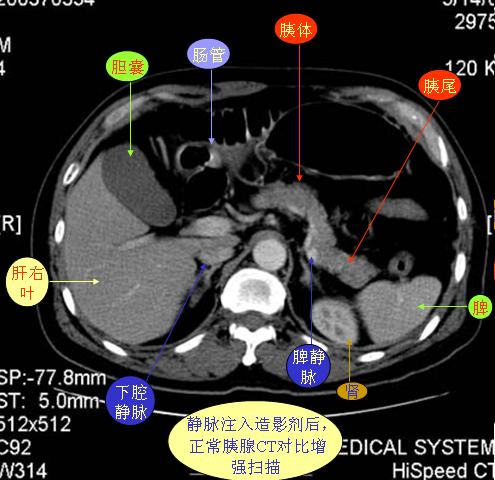

腹部ct解剖与基本病变